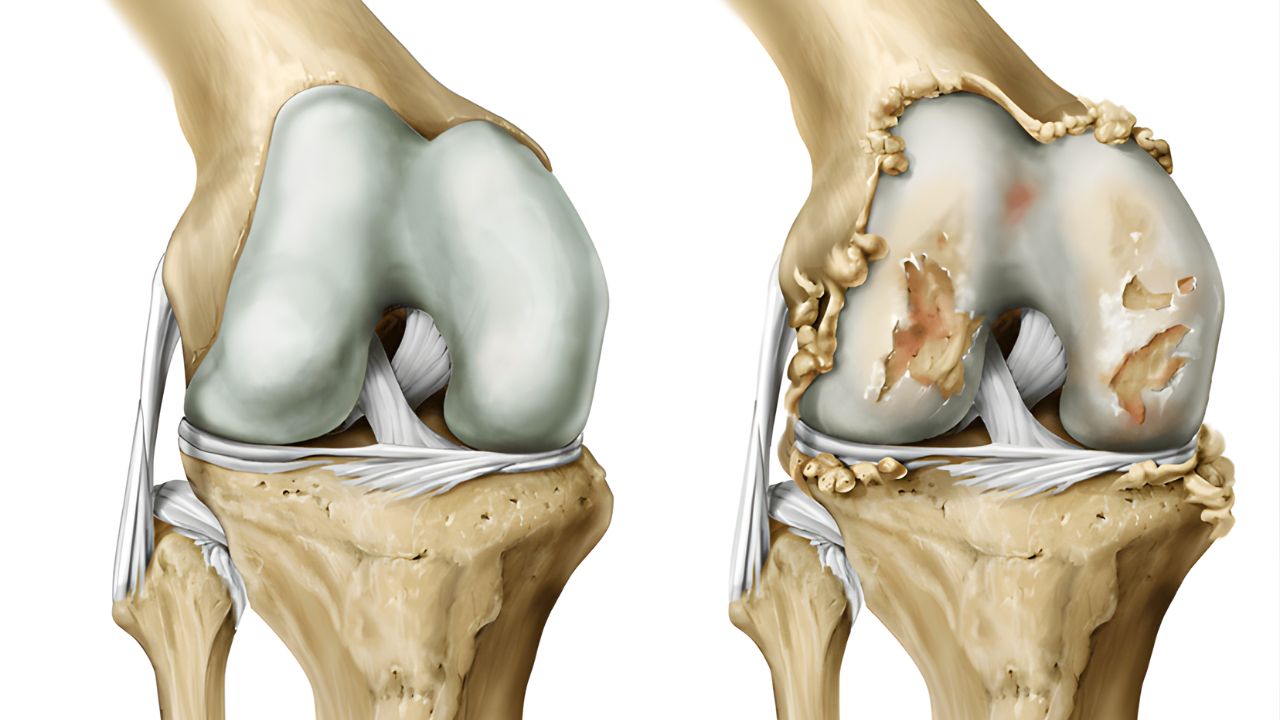

Artrose de Joelho Agendar consulta A artrose de joelho, também conhecida como osteoartrite, é uma doença degenerativa crônica que afeta a articulação do joelho. Ela